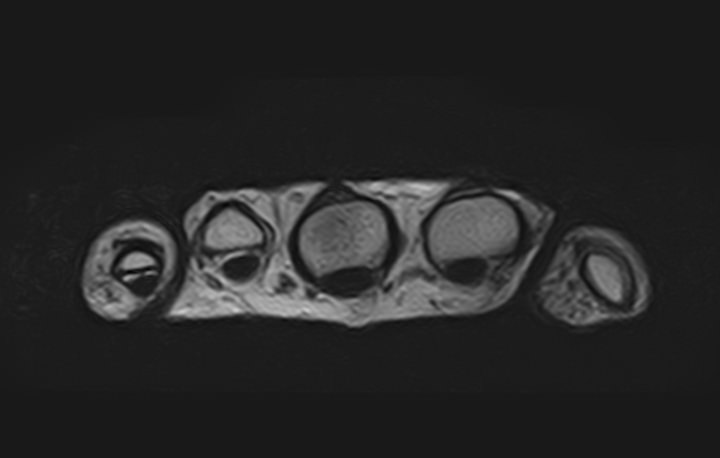

Современным и высокоточным методом диагностики заболеваний кистей рук является магнитно-резонансная томография. МРТ дает наиболее полную информацию о состоянии костей, суставов, связок, сухожилий, нервных волокон и мягких тканей кисти. Дополнительным преимуществом МРТ является ее безопасность, так как в основе метода лежит использование внешнего магнитного поля без применения ионизирующего излучения. При необходимости это позволяет выполнять исследование неоднократно в течение короткого периода времени.

Клиника «Доступная медицина» располагает новейшим 32-канальным высокопольным томографом закрытого типа TOSHIBA VANTAGE TITAN 1,5 Тесла, который позволяет получать изображения зоны кистей рук с высокой степенью детализации. Данные, полученные по результатам МР томографии, дают возможность врачу поставить точный достоверный диагноз и назначить своевременное лечение.

МРТ кисти руки – это высокоспецифичный метод визуализации мышц, связок, хрящей, костного мозга, жировой ткани.

С его помощью обнаруживаются:

• деструктивные изменения в суставах;

• утолщение синовиальных оболочек, выстилающих суставные полости;

• воспалительные выпоты ;

• краевые дефекты костной ткани;

• растяжения, разрывы связок , сухожилий сгибателей — разгибателей;

• субхондральные кисты (деградация кости вокруг суставного хряща);

• доброкачественные новообразования мягких тканей пальцев кисти (нодулярный теносиневит, сухожильный ганглий);

• злокачественные опухоли (остеосаркомы, мягкотканные саркомы ).

МРТ сухожилий и мягких тканей кисти руки помогает с постановкой окончательного диагноза, установленного при помощи других методик.